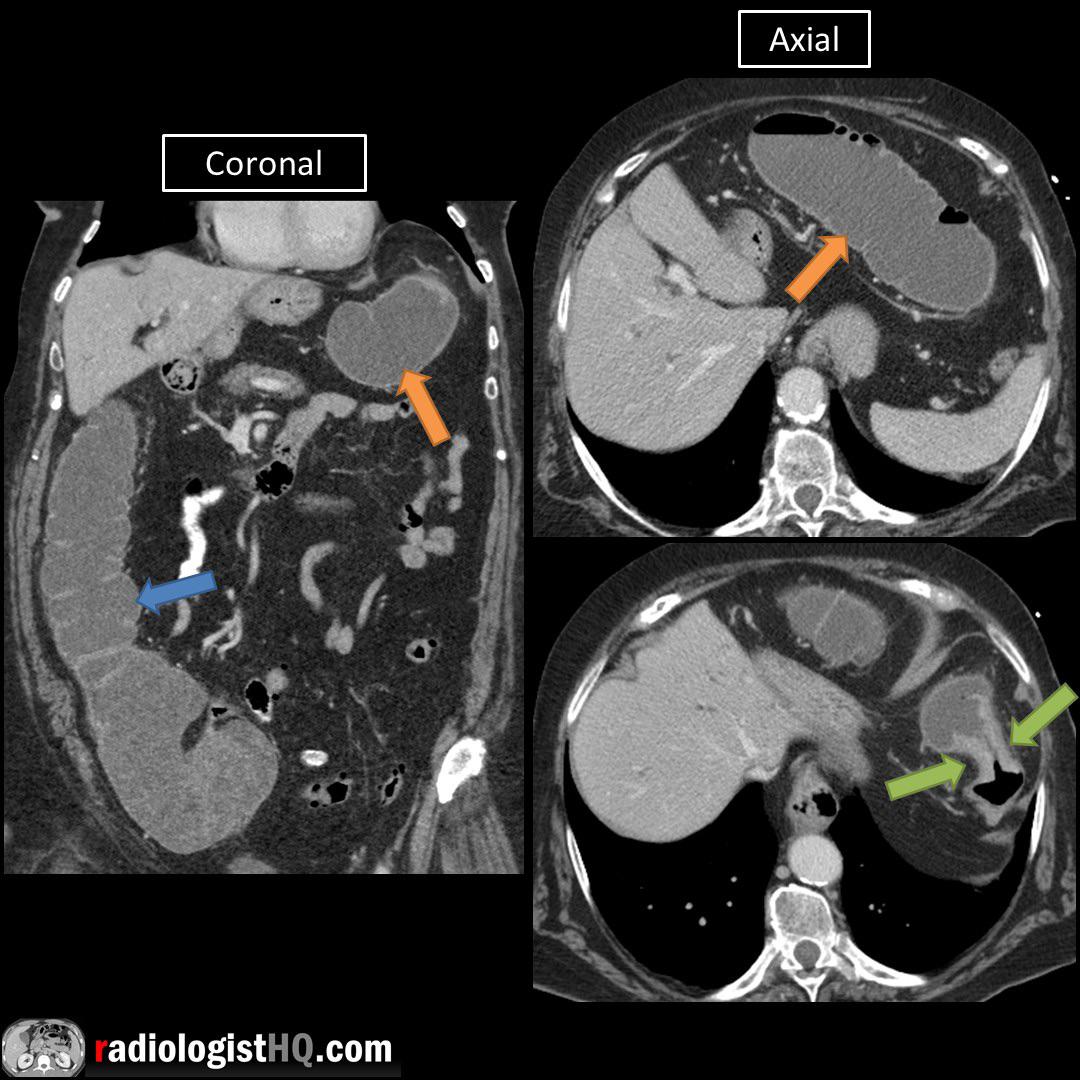

Apple Core Ct Scan . Ct scanning can help identify the tumor site, the size of the tumor, and locoregional and metastatic. There is demonstration of an apple core lesion within the sigmoid colon which correlated to the masslike structure seen on the prior ct. Ct scanning plays an integral role in the staging of colon cancer. The apple core sign, also known as a napkin ring sign, is most frequently associated with constriction of the lumen of the colon by a. Tumors of the right colon can grow very large before causing symptoms such. Tumors of the right colon can grow very large before causing symptoms such as obstruction.

The apple core sign, also known as a napkin ring sign, is most frequently associated with constriction of the lumen of the colon by a. Tumors of the right colon can grow very large before causing symptoms such as obstruction. Ct scanning can help identify the tumor site, the size of the tumor, and locoregional and metastatic. Ct scanning plays an integral role in the staging of colon cancer. Tumors of the right colon can grow very large before causing symptoms such. There is demonstration of an apple core lesion within the sigmoid colon which correlated to the masslike structure seen on the prior ct.

Apple Core Ct Scan Ct scanning plays an integral role in the staging of colon cancer. Tumors of the right colon can grow very large before causing symptoms such. There is demonstration of an apple core lesion within the sigmoid colon which correlated to the masslike structure seen on the prior ct. The apple core sign, also known as a napkin ring sign, is most frequently associated with constriction of the lumen of the colon by a. Tumors of the right colon can grow very large before causing symptoms such as obstruction. Ct scanning plays an integral role in the staging of colon cancer. Ct scanning can help identify the tumor site, the size of the tumor, and locoregional and metastatic.